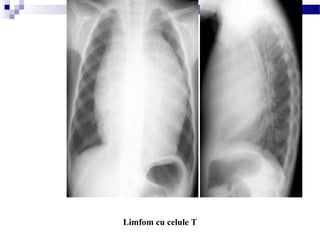

Limfom cu celule T

Radiografie toracică, inciden ă PA i profilț ș (de observat faptul că hilul se

poate vedea prin transparen a masei, fapt ce arată ca masa nu este hilarăț )

Pe profil nu se vede nimic patologic posterior de aceasta.